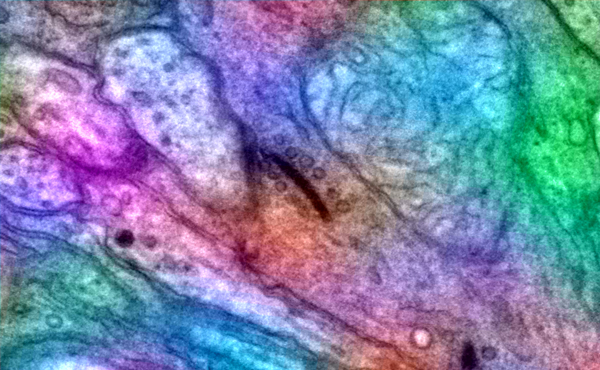

Keratoprosthesis

This image is from a patient has a keratoprosthesis or artificial cornea. Photograph was made by James Gilman of the Moran Eye Center using a sclerotic scatter illumination with a Zeiss photo slitlamp and a Nikon D-1X camera.